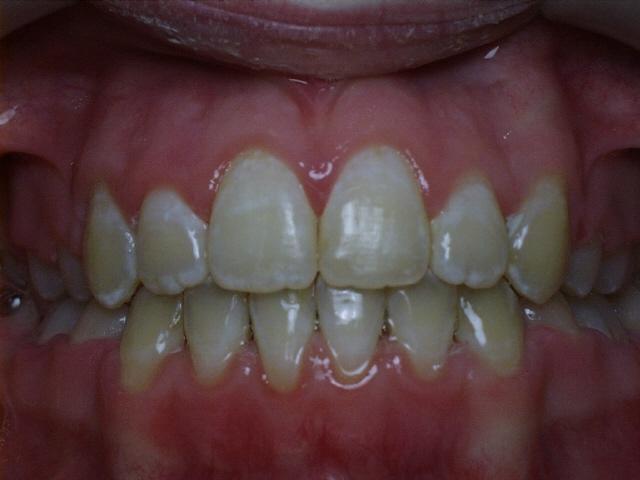

Moderate crowding with a severe overbite.  Treatment time was 20 months.  This case required the extraction of two upper permanent teeth.  The molars were class 2 (upper molars too far forward at the start of treatment).

Before  mrao1.jpg (28593 bytes)     mrao3.jpg (29394 bytes)  After